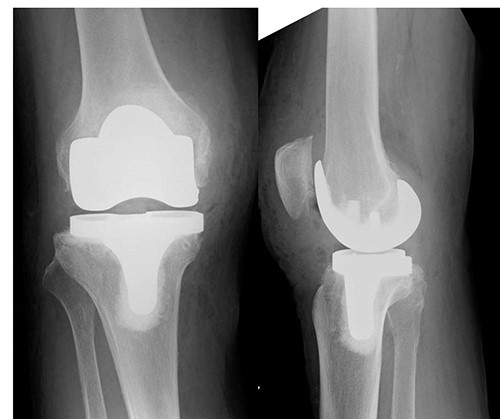

An 82-year-old woman underwent bilateral TKA for Grade IV knee osteoarthritis. The surgery was performed through a midline gentle curved incision and a trivector approach. Cemented medial pivot implants (Medacta® GMK-Sphere, Medacta International: Castel S. Pietro, Switzerland) were placed. No resurfacing was performed because of the anterior tilt of the patella during surgery. Recovery was uneventful, and the patient was able to walk comfortably without support 3 weeks post-operatively. After 1 week, she felt pain in the right knee joint without any specific triggers. Her gait was stiff, and she needed support to walk. Range of motion testing showed knee extension of −35° and knee flexion of 80°. There was no warmth or redness in the right knee. Tenderness at the tibial tuberosity was mild, and radiographic examination showed patellar alta (Fig. 1).

After hemostasis, the wound closed in layers. The patient had a cylinder cast for 4 weeks and was allowed full weight-bearing. At 4 weeks post-operatively, the knee was immobilized, and dynamic quadriceps exercises were initiated. The patient regained pain-free motion from 0° to 100° without extension lag. She could walk without a cane 3 months post-operatively. X-rays also showed no patellar alta (Fig. 5).

X-ray, 3 months post-operatively, did not show any patellar alta.